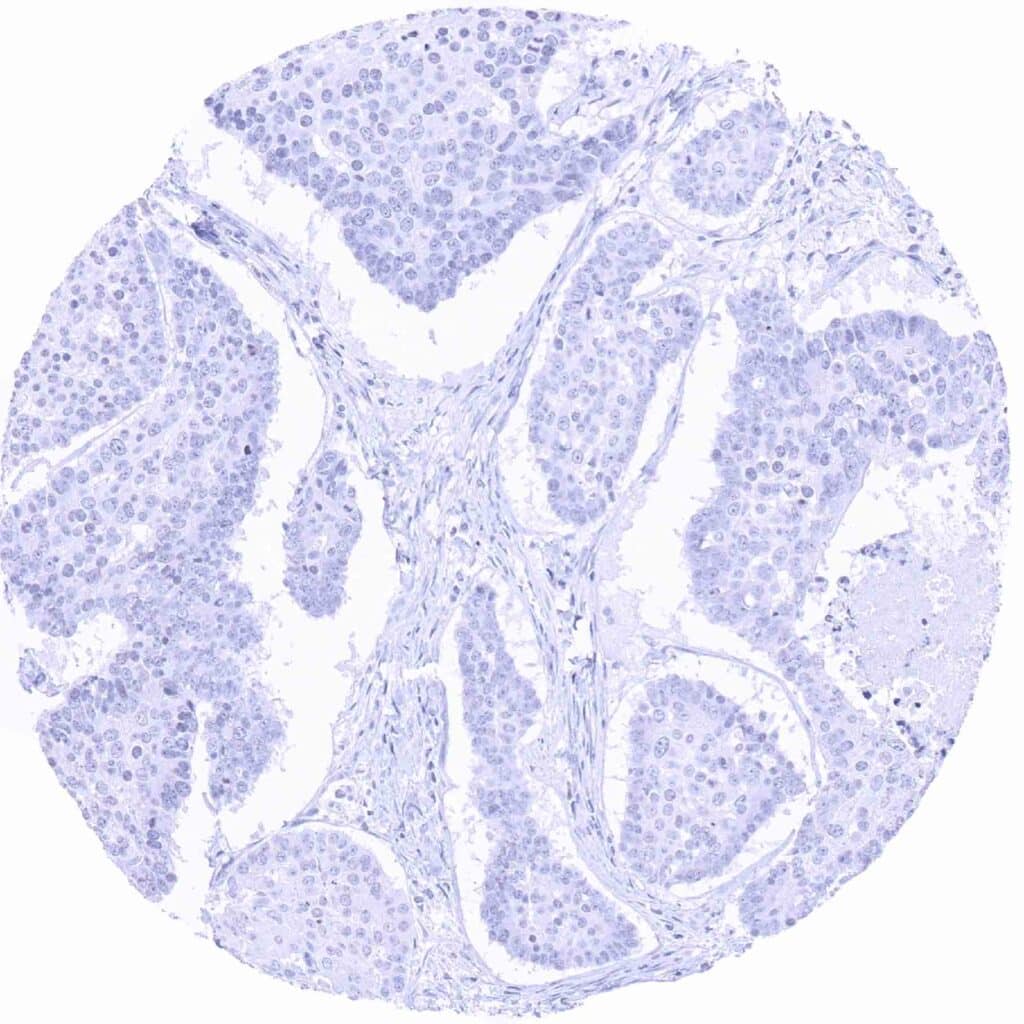

Pancreas – Prostein negative neuroendocrine tumor